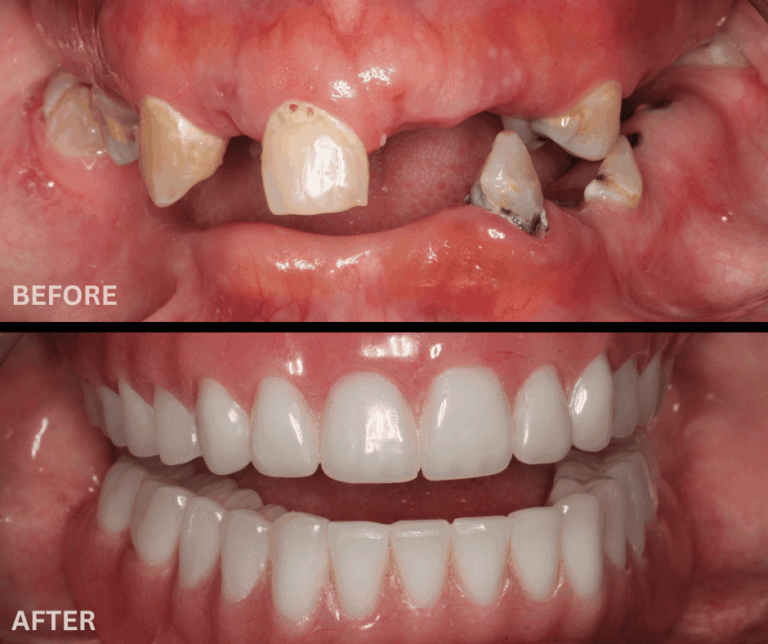

Mike's Smile